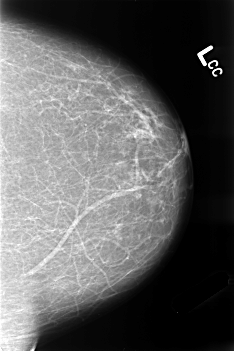

B_3250_1.LEFT_CC

LEFT_CC LINES 4552 PIXELS_PER_LINE 3032 BITS_PER_PIXEL 12 RESOLUTION 50 NON_OVERLAY

LEFT_MLO LINES 4560 PIXELS_PER_LINE 3064 BITS_PER_PIXEL 12 RESOLUTION 50 NON_OVERLAY